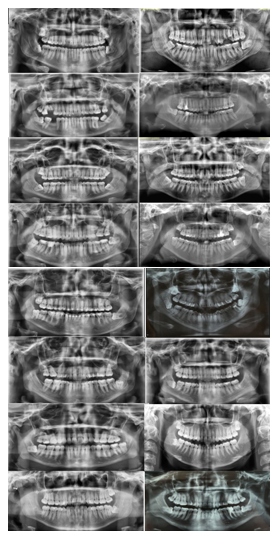

The inclusion criteria considered were ability to understand and consent to participation in clinical trial, expressed by signing the Free and Informed Consent Form (FICF), age between 18 and 40 years, good physical and mental health, not being pregnant, with clinical and radiographic diagnosis impacted lower third molar with indication surgical removal in vertical, mesioangular, or horizontal position according to classification of Winter23 and Class II A, Class II B, or Class III B according to classification of Pell & Gregory,24 as shown in participants' panoramic radiographs illustrating impacted lower third molar in vertical, mesioangular, or horizontal positions (Figure 1).

Figure 1 Panoramic views of impacted lower third molars in vertical, mesioangular, or horizontal positions.